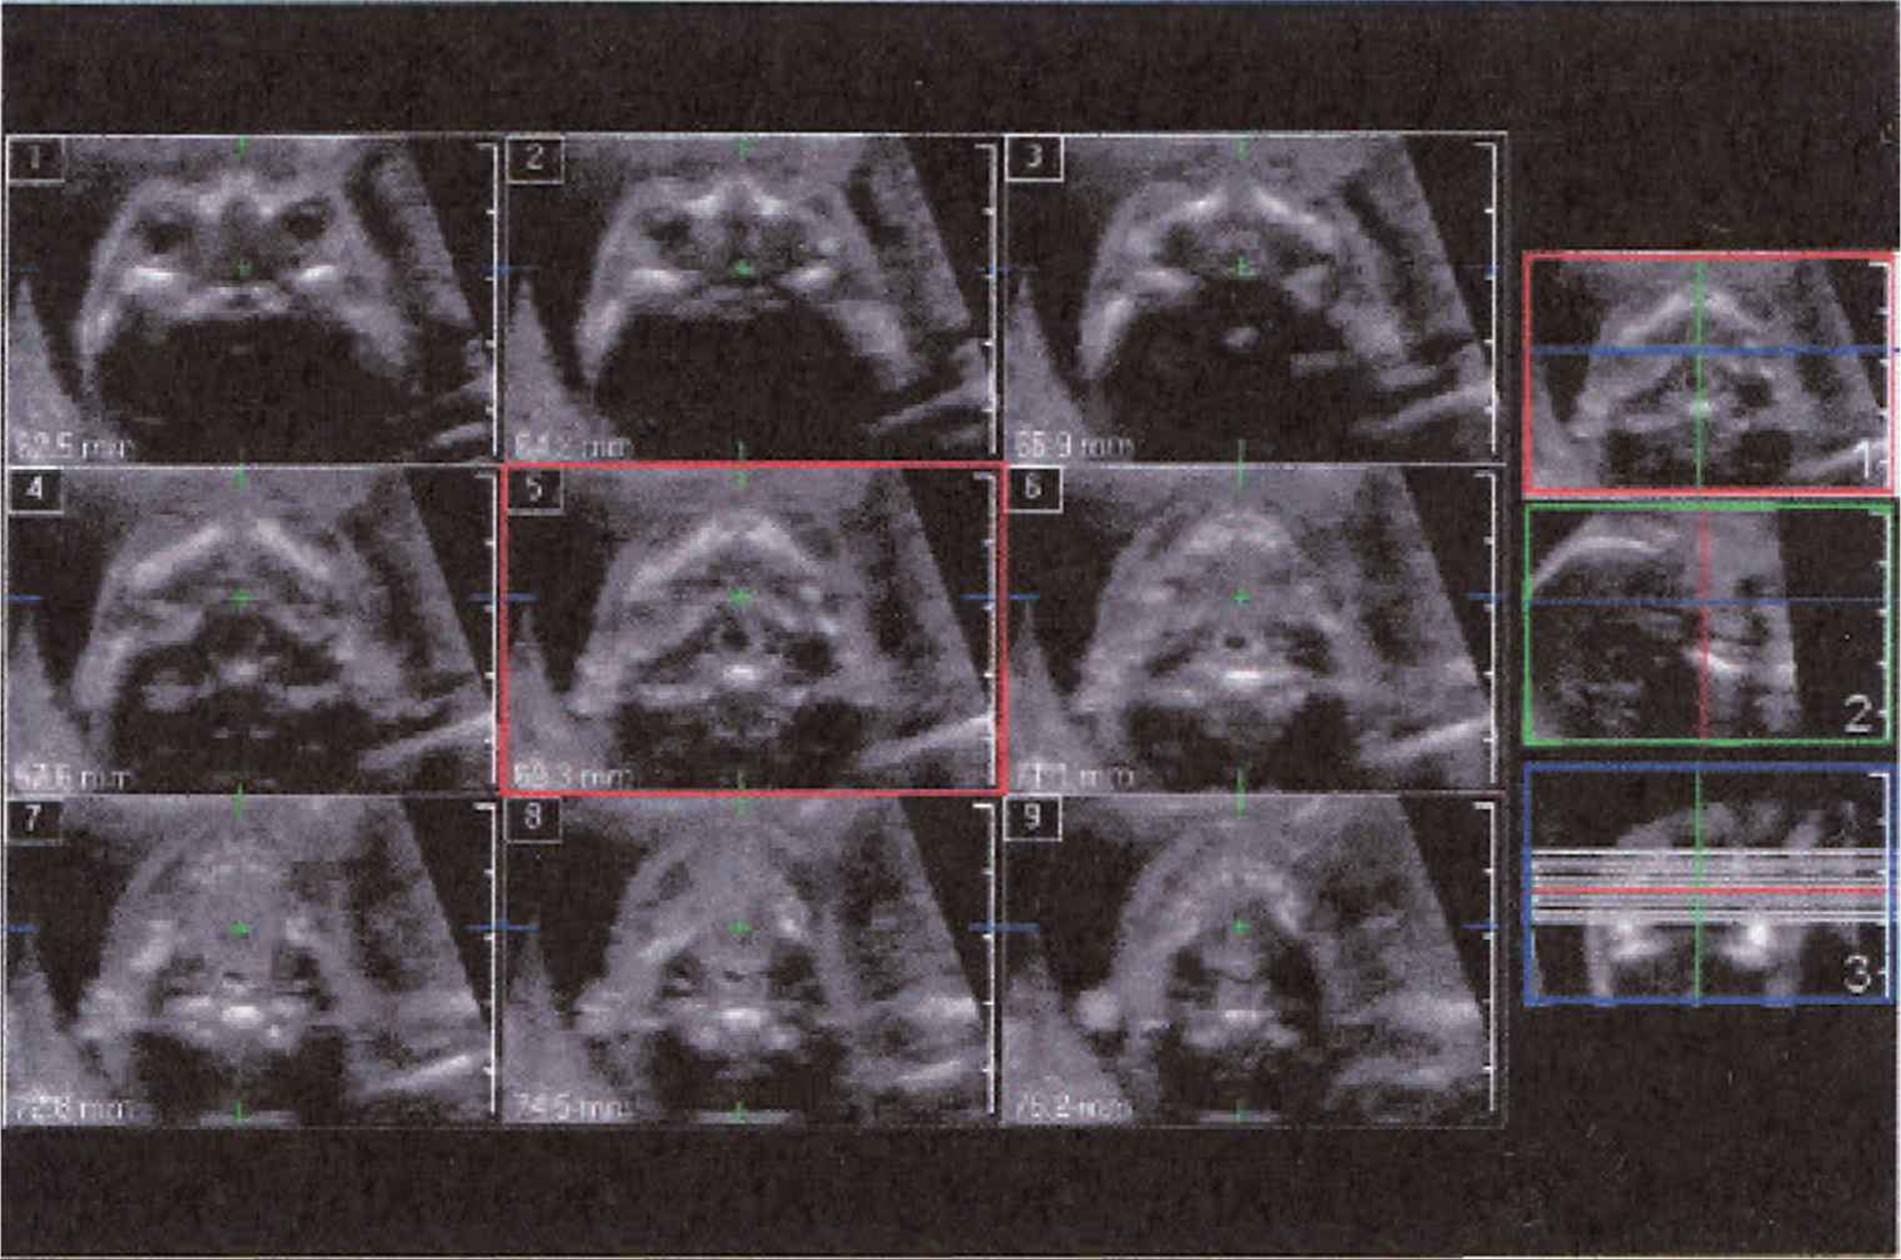

This layout of multiplanar reconstructed images can be varied to emphasize the volumetric images as the largest one displayed. Three-dimensional images can be manipulated to emphasize the surface (surface rendering) or the entire volume (volume rendering). The ability to visualize the structure from a selectable scan plane is particularly helpful when such planes cannot be readably obtainable from a 2D image. This is particularly true in the evaluation of the fetal heart when obtaining an optimal image of the outflow tracts, this may not be possible on 2D acquisition but quite possible with 3D. Another new feature is the ability to display multiple tomographic images (Philips’ iSlice) obtained in selectable intervals and slice thicknesses.

FIGURE 8–10. iSlice 3D showing normal fetal palate. (Courtesy of Philips Healthcare.)

FIGURE 8–11. iSlice 3D showing normal fetal palate and mandible. (Courtesy of Philips Healthcare.)